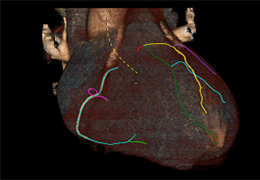

ANYTHINK 经导管主动脉瓣膜置换术分析系统